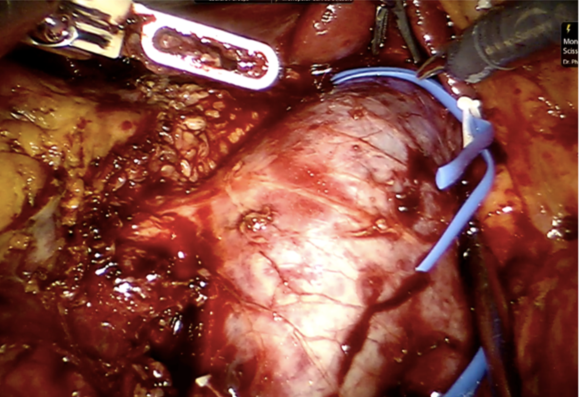

Bệnh nhân đã được phẫu thuật nội soi với robot hỗ trợ để lấy toàn bộ thận và khối bướu trong lòng tĩnh mạch chủ bụng trong 5 giờ với thời gian khống chế tuần hoàn (kẹp tĩnh mạch lớn nhất trong cơ thể) trong vòng 32 phút, truyền 2 đơn vị máu sau mổ, chăm sóc tại phòng hồi tỉnh 24 giờ và xuất viện vào ngày thứ 6 sau phẫu thuật trong tình trạng sức khỏe ổn định.

Theo các chuyên gia, phẫu thuật lấy chồi bướu trong lòng tĩnh mạch chủ là kỹ thuật đỉnh cao của phẫu thuật ngoại tiết niệu, đòi hỏi bác sĩ phẫu thuật giàu kinh nghiệm có kỹ năng chuyên môn rất cao.

Từ trước cho đến nay, tại Việt Nam, khi phát hiện ung thư thận có chồi bướu trong lòng tĩnh mạch chủ, bệnh nhân đều được can thiệp điều trị bằng phương thức mổ mở. Với thành công của ca phẫu thuật nội soi robot, Bệnh viện Bình Dân đã hoàn thiện được tất cả các phẫu thuật khó nhất trong chuyên ngành ngoại tiết niệu. Đây là một can thiệp chuyên sâu nhưng ít xâm hại: đường mổ nhỏ, ít đau, hạn chế mất máu, hồi phục sớm và rút ngắn thời gian nằm viện, góp phần tăng chất lượng cuộc sống cho người bệnh.